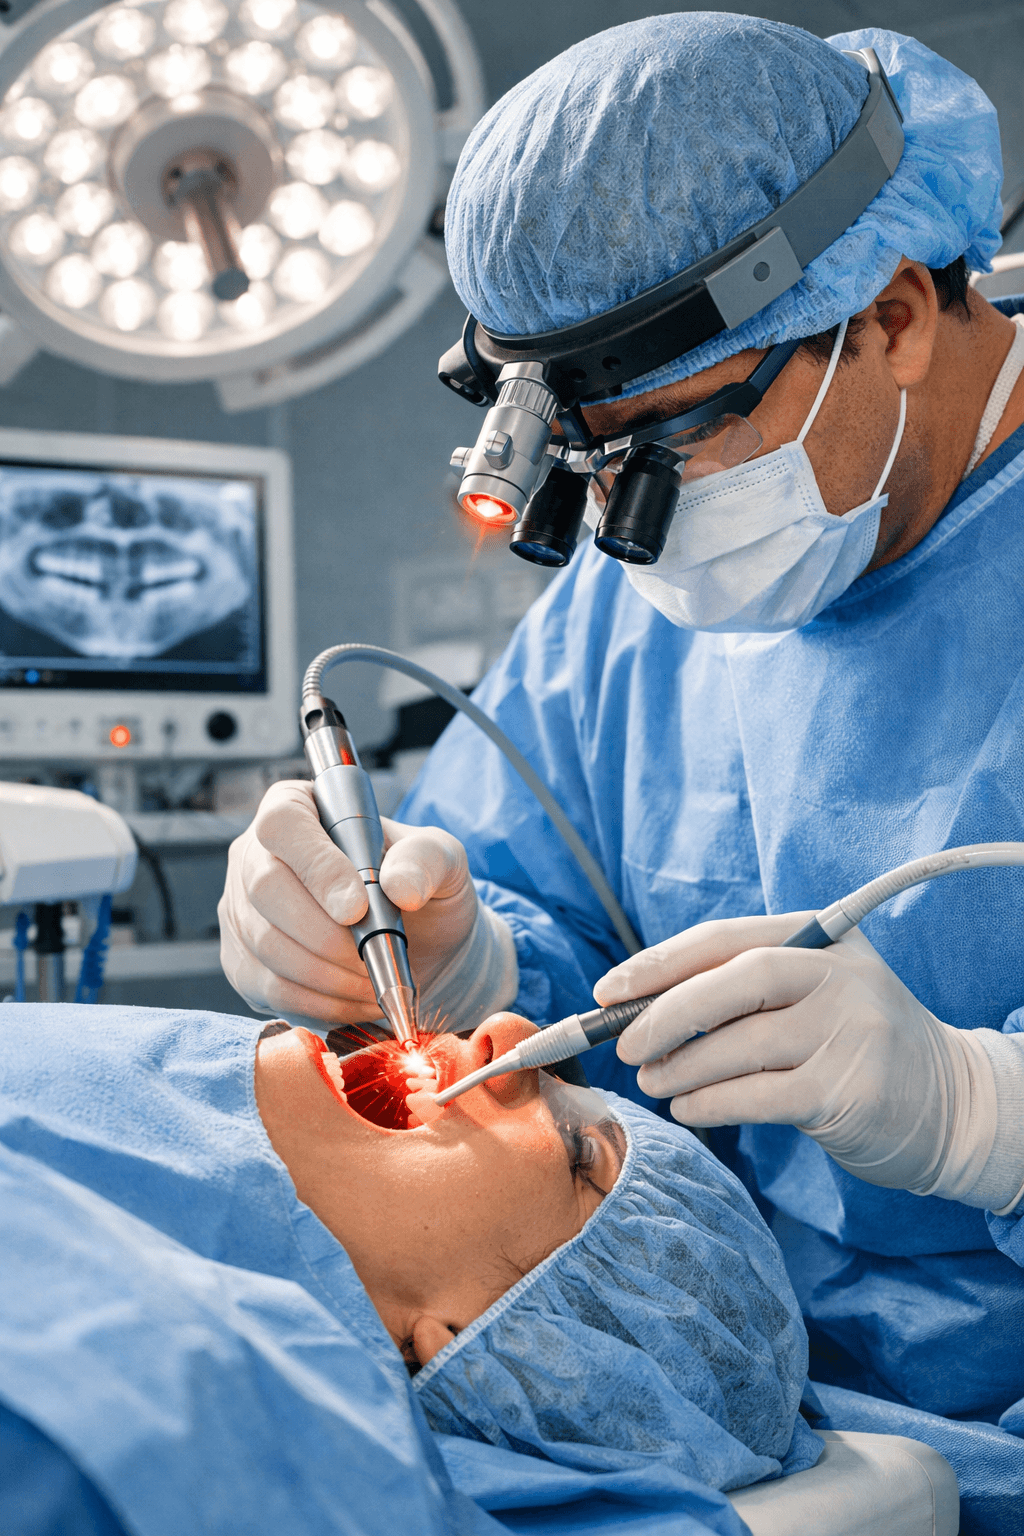

Robust Medical Diode Lasers, Fibres and Staplers

Our Product Applications

Minimally invasive procedures across multiple surgical specialities